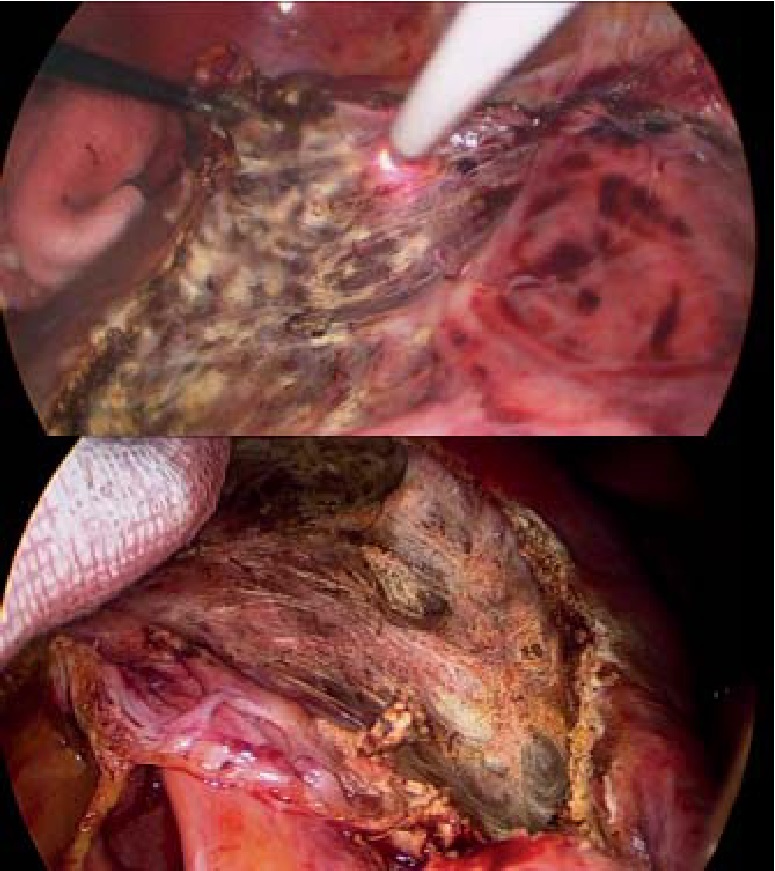

В параумбиликальной области установлен лапаропорт с оптической системой. При ревизии – в брюшной полости выпота нет. В проекции IV, V и VIII сегментов печени визуализирована киста размерами 18×18×12 см (рис. 2).

Рис. 2. Интраоперационная картина кисты печени

Выполнена пункция кисты печени – получено около 2000 мл прозрачного экссудата. Стенки кисты иссечены с помощью аппарата «LigaSure». Ложе кисты тщательно обработано аргоноплазменной коагуляцией (рис. 3). Аргон под действием электрического поля достаточно легко ионизируется и превращается в плазму, которая направляется в ткани с наименьшим электрическим сопротивлением, вызывая таким образом коагуляцию. Данная методика обработки ложа кисты имеет ряд преимуществ перед обработкой электрокоагуляцией: отсутствие прилипания и минимальная травматизация окружающих тканей, стойкая, но при этом неглубокая (до 3 мм) коагуляция, а также минимальное дымообразование, что очень важно в лапароскопической хирургии. Кроме того, отмечается антимикробное воздействие аргоновой плазмы на обрабатываемую поверхность при бесконтактном использовании [1, 17].

Рис. 3. Вид операционного поля во время и после обработки аргоноплазменным потоком

Затем выделены раздельно, клипированы и пересечены пузырный проток и пузырная артерия. Выполнена холецистэктомия «от шейки». Ложе желчного пузыря также обработано аргоноплазменной коагуляцией. Произведены дренаж к ложу желчного пузыря и два дренажа к ложу кисты печени, осуществлён контроль гемостаза, холестаза и инородных тел.

Желчный пузырь и стенки кисты извлечены из брюшной полости в контейнере (препараты отправлены на патогистологическое исследование) (рис. 4).